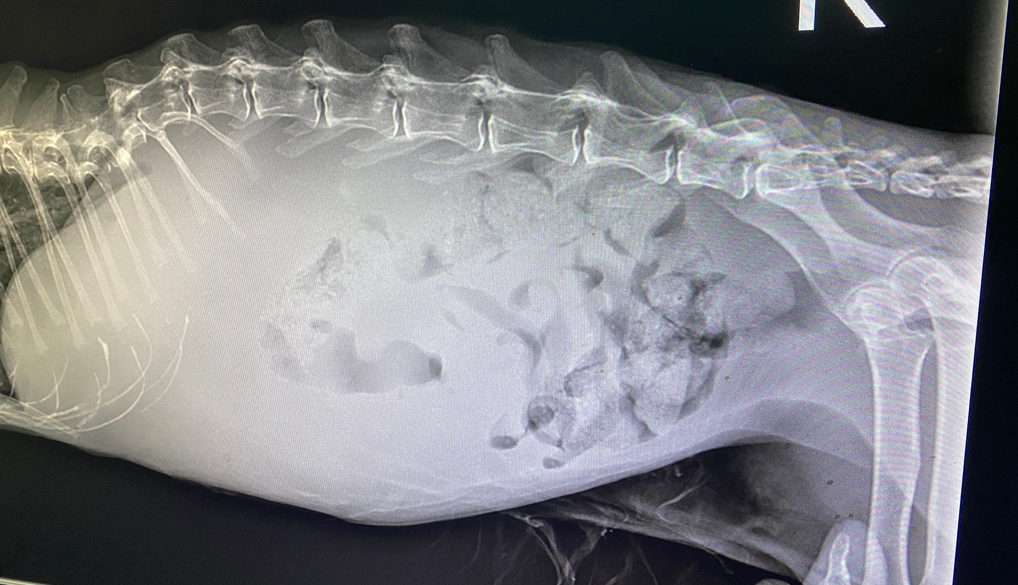

종양이 뒷다리쪽 혈관을 누르고 있어서 뒷다리가 붓고 자꾸 한쪽으로 넘어집니다. 당뇨질환을 가지고 있는데 인슐린을 안맞아도 당이 자꾸 떨어져요?

종양이 오른쪽 뒷다리 혈관을 누르고 있어서 뒷다리가 붓고 자꾸 일어나면 한쪽으로 넘어집니다.

당뇨질환을 가지고 있는데 인슐린을 안맞아도 당이 자꾸 떨어지는데 이제는 나이도 있는데 당조절도 안되고 간이나 췌장기능이 제대로 못해서 종양이 당성분을 다 빨이 들이는것 같다고 얘기하는데 이에 대한 치료 방법은 없을까요??

나이때문에 제거수술도 못하고 종양은 점점 커지고 이미 종양이 장기들을 다 뒤로 밀어버려서 아이도 힘들어하구요 ㅠ